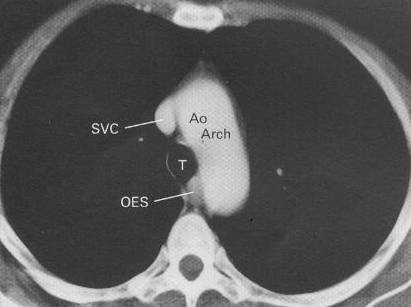

key structures on CT in the mediastinum:

CT of normal mediastinum. Five 1-cm thick sections have been selected to show the

important anatomical features (AE). The level of each section is illustrated in the

diagram. A.Ao = ascending aorta, AV = azygos vein, D.Ao = descending aorta, IA =

innominate artery, LCA = left carotid artery, LIV = left innominate vein, LPA = left

pulmonary artery, LSA = left subclavian artery, MPA = main pulmonary artery, Oes =

oesophagus, RIV = right innominate vein, RPA = right pulmonary artery, SVC = superior vena

cava, T = trachea, RA = right atrium, LA = left atrium, RVO = right ventricular outflow

tract.